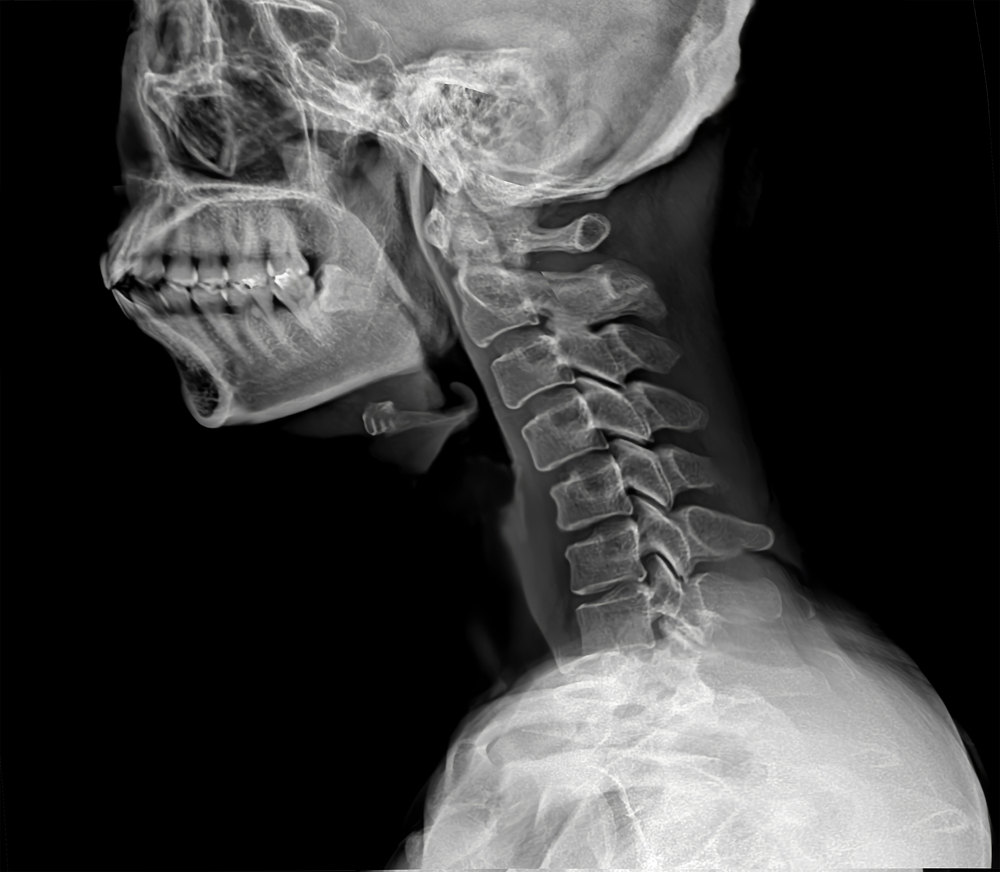

거북목증후군

거북목은 경추의 C자 커브가 무너지면서

목이 앞으로 나온 상태를 말합니다.